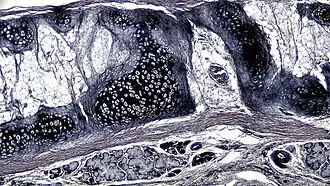

| .jpg) A cross section of mammalian elastic cartilage | |

Elastic cartilage is histologically similar to hyaline cartilage but contains many yellow elastic fibers lying in a solid matrix. These fibers form bundles that appear dark under a microscope. The elastic fibers require special staining since when it is stained using haematoxylin and eosin (H&E) stain it appears the same as hyaline cartilage.[3] Verhoeff van Geison stains are used (giving the elastic fibers a black color), but aldehyde fuchsin stains, Weigert's elastic stains, and orcein stains also work.[3] These fibers give elastic cartilage great flexibility so that it is able to withstand repeated bending. Similarly to hyaline one or multiple chondrocytes lie between the spaces (or lacunea) in the fibres.[2] The chondrocytes only make up 2% of the tissue's volume.[2] Chondrocytes and the extracellular matrix are contained in an outerlayer named the perichondrium[2] (which is a layer of dense irregular connective tissue that surrounds cartilage which is independent of the joint).[3] It is found in the epiglottis (part of the larynx), and the pinnae (the external ear flaps of many mammals). Elastin fibers stain dark purple/black with Verhoeff's stain.